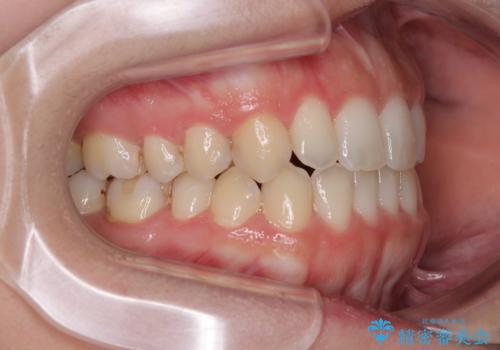

【モニター】オープンバイトをインビザライン矯正で治す

- 前歯の開咬を気にして来院された患者様です。

開咬の治療は、前歯を閉じるように動かすとともに、上下臼歯を圧下(骨内にめり込ませる)させることで進めて行きます。

インビザラインは臼歯の圧下を効果的に行えるため、インビザラインを用いて矯正治療を行うこととしました。